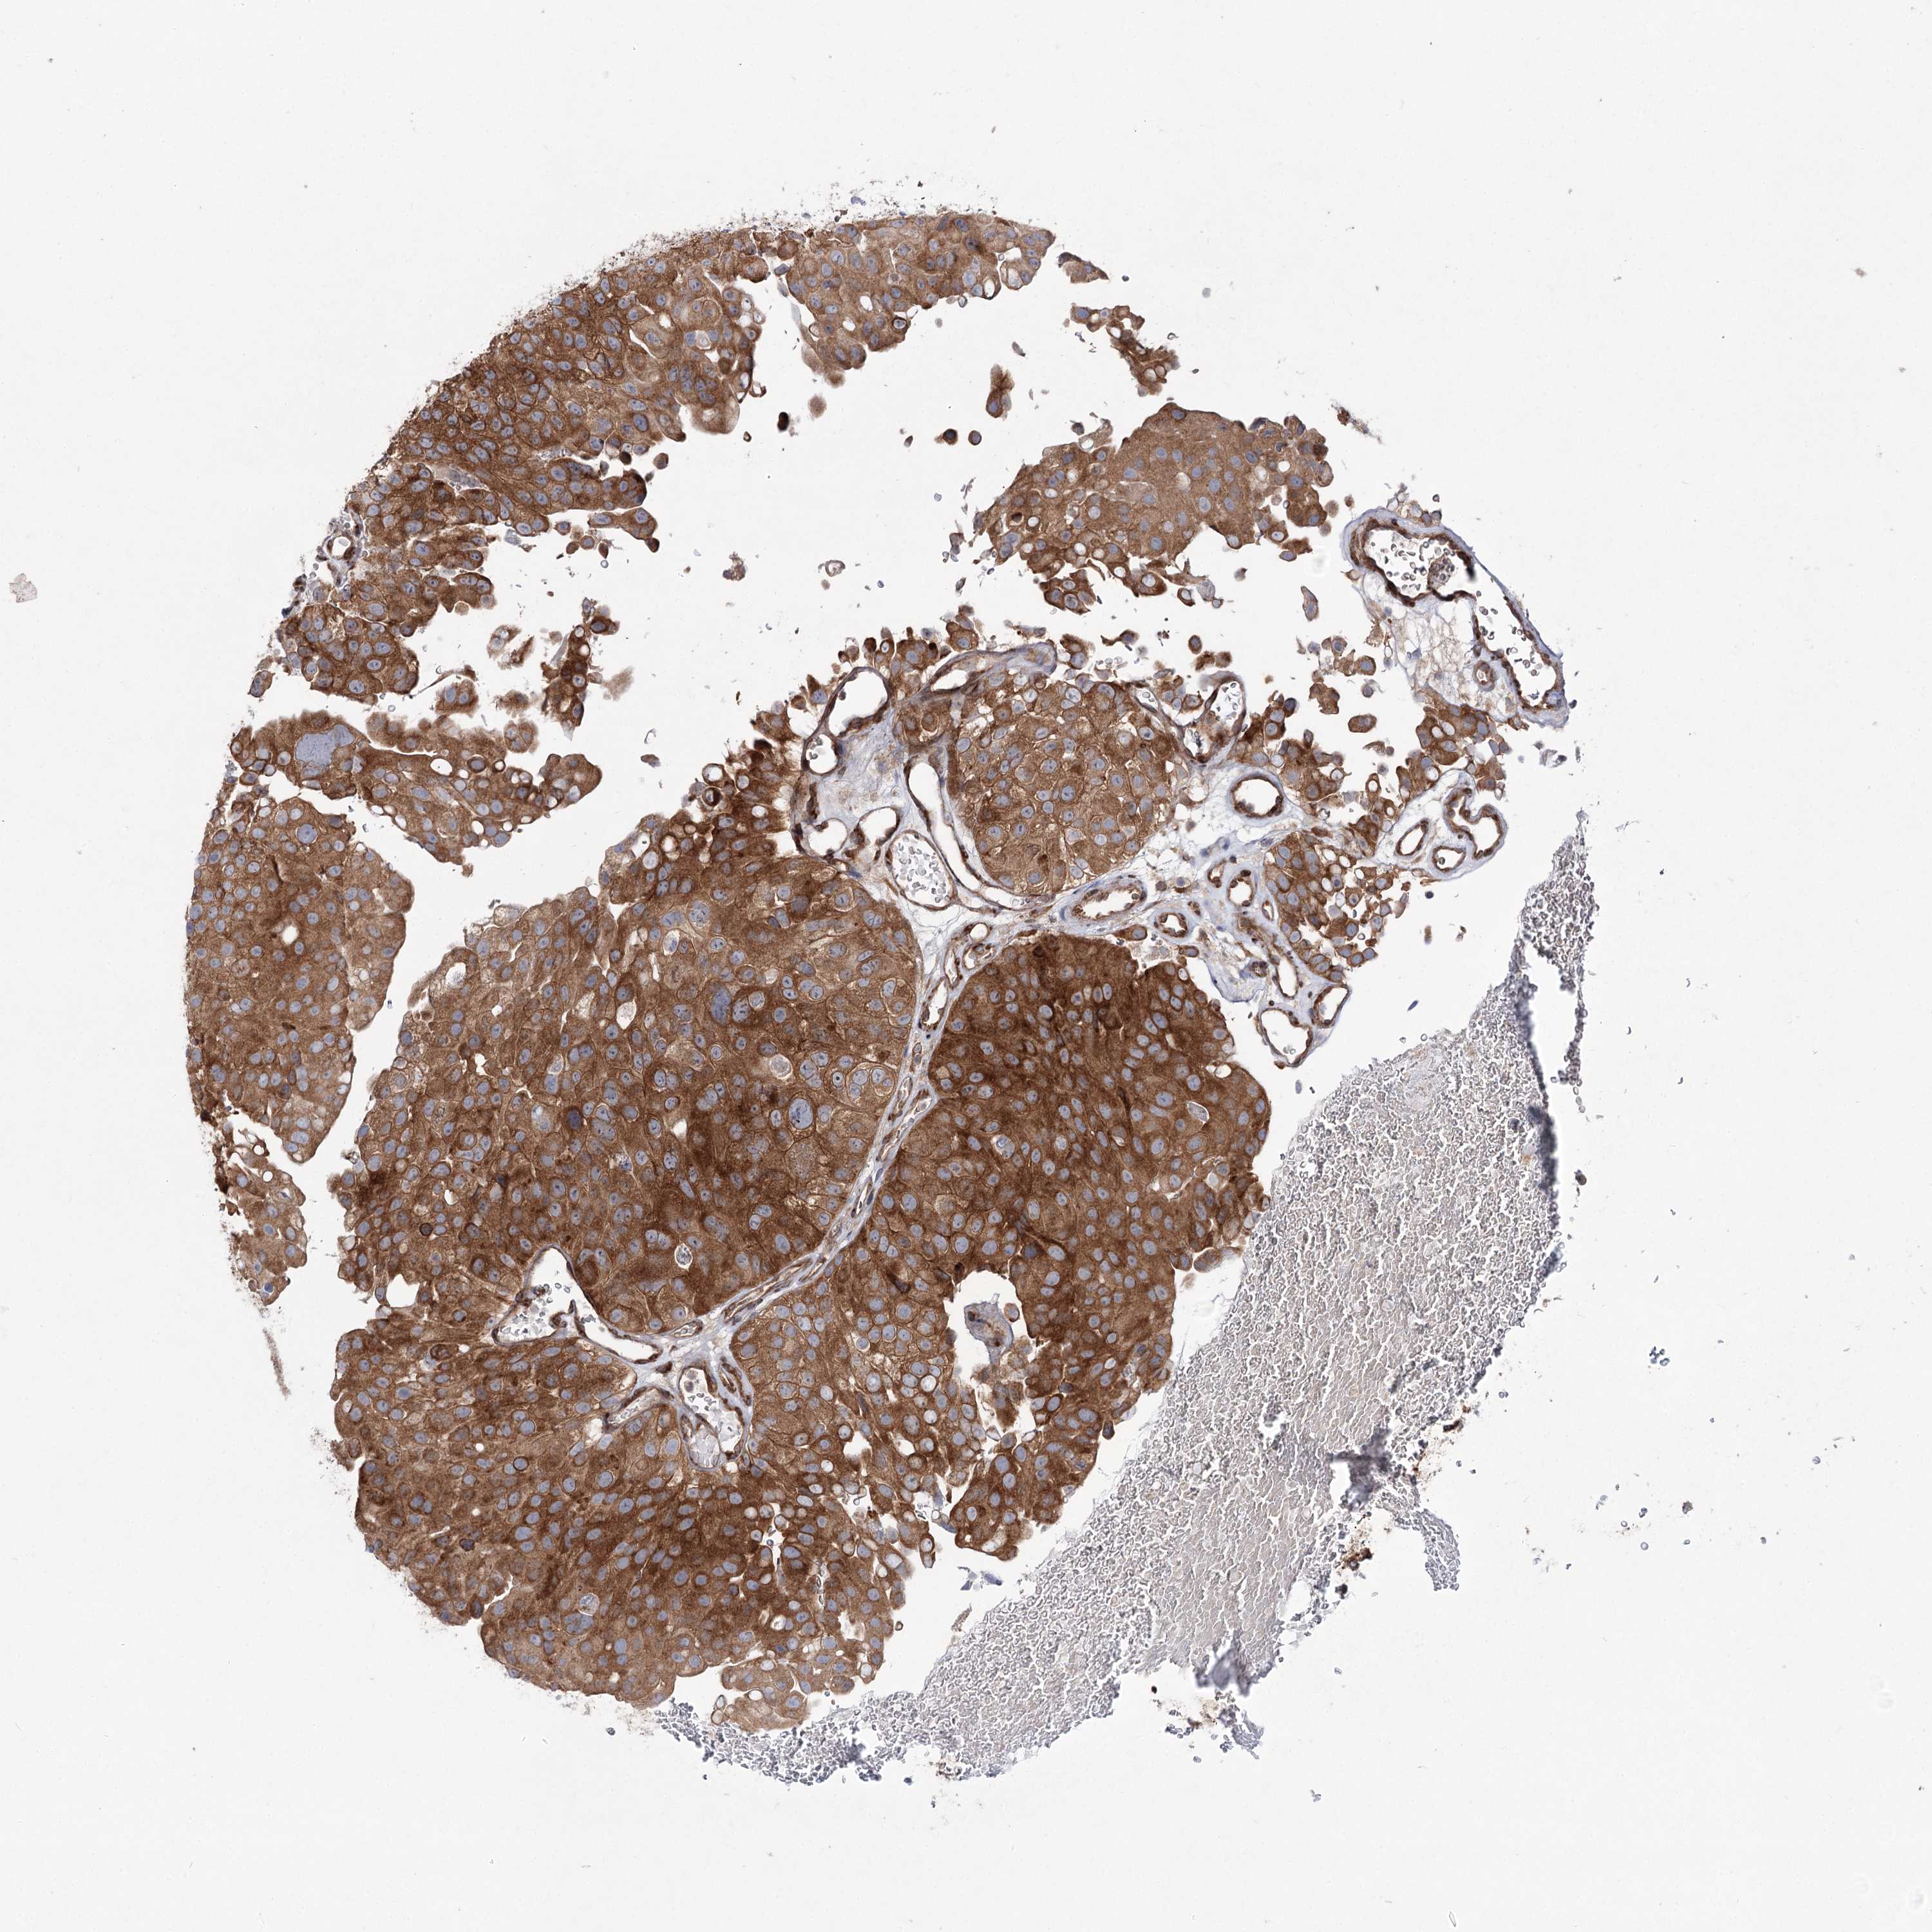

UROTHELIAL CANCER - Protein expressioni

A mouse-over function shows sample information and annotation data. Click on an image to view it in a full screen mode. Samples can be filtered based on level of antibody staining by selecting one or several of the following categories: high, medium, low and not detected. The assay and annotation is described here.

Note that samples used for immunohistochemistry by the Human Protein Atlas do not correspond to samples in the TCGA dataset.

Antibody stainingi

Antibody staining in the annotated cell types in the current human tissue is reported as not detected, low, medium, or high, based on conventional immunohistochemistry profiling in selected tissues. This score is based on the combination of the staining intensity and fraction of stained cells.

Each image is clickable and will lead to virtual microscopy that enables deeper exploration of all samples and also displays staining intensity scores, fraction scores and subcellular localization as well as patient and tissue information for each sample.

Antibody HPA037847

Staining

High

Medium

Low

Not detected

Intensity

Strong

Moderate

Weak

Negative

Quantity

>75%

75%-25%

<25%

None

Location

Nuclear

Cytoplasmic/membranous

Cytoplasmic/membranous,nuclear

Urothelial carcinoma, High grade

Urothelial carcinoma, Low grade

Urothelial carcinoma, NOS